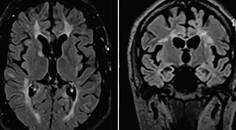

Critical Bilateral Carotid Artery Disease Presenting as Hemichorea

Margarida Ferro, MD, MSc; Marcos Gil Veiga, MD, DMD, MScMargarida Ferro, MD, MSc; Marcos Gil Veiga, MD, DMD, MSc - Movement Disorders